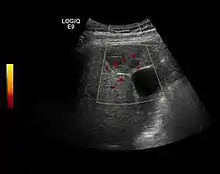

Liver metastases

US examination is required to detect liver metastases in patients with oncologic history. In addition, the method can incidentally detect metastases in asymptomatic patients. Early identification (small sizes, small number) is important to establish an optimal course of treatment which can be complex (chemotherapy, radiofrequency ablation, surgical resection) but welcomed. In addition, discrimination of synchronous lesions that have a different nature is also important knowing that up to 25–50% of liver lesions less than 2 cm detected in cancer patients may be benign . US sensitivity for metastases detection varies depending on the examiner's experience and the equipment used and ranges between 40–80% . Sensitivity is conditioned by the size and acoustic impedance of the nodules. For a lesion diameter below 10 mm US accuracy is greatly reduced, reaching approx. 20%. Other elements contributing to lower US performance are: excessive obesity, fatty liver disease, hypomobility of the diaphragm, and certain patterns of hyperechoic or isoechoic metastases that can be overlooked or can mimic benign conditions. Conventional US appearance of metastases is uncharacteristic, consisting of circumscribed lesions, with clear, imprecise or "halo" delineation, with homogeneous or heterogeneous echo pattern. They can be single (often liver metastases from colonic neoplasm) or multiple. Echogenity is variable. When increased, they can compress the bile ducts (which may be dilated) and the liver vessels. Liver involvement can be segmental, lobar or generalized. In this situation a pronounced hepatomegaly occurs. Generally, metastases have non-characteristic Doppler vascular pattern, with few exceptions (carcinoid metastases). Cyst-adenocarcinoma metastases due to semifluid content may have a transonic appearance. When increasing, they can result in central necrosis. CEUS examination is a real breakthrough for detection and characterization of liver metastases.

Increased performance is based on identifying specific vascular patterns during the arterial phase and seeing metastases in contrast to normal liver parenchyma during the sinusoidal phase. CEUS increased accuracy is due to the different behavior of normal liver parenchyma (captures CA in Kuppfer cells) against tumor parenchyma (does not contain Kuppfer cells, therefore CEUS appearance is hypoechoic). To this adds the particularities of intratumoral circulation represented by a reduced arterial bed compared to that of the surrounding normal liver and the absence of the portal vessels . In terms of vascularity, metastases can be hypovascular (in gastric, colonic, pancreatic or ovarian adenocarcinomas) with hypoechoic pattern during arterial phase, and similar during portal venous and late phases, respectively hypervascular (neuroendocrine tumors, malignant melanoma, sarcomas, renal, breast or thyroid tumors) with hyperechoic appearance during arterial phase, with washout during the portal venous phase and hypoechoic pattern 30 seconds after injection.